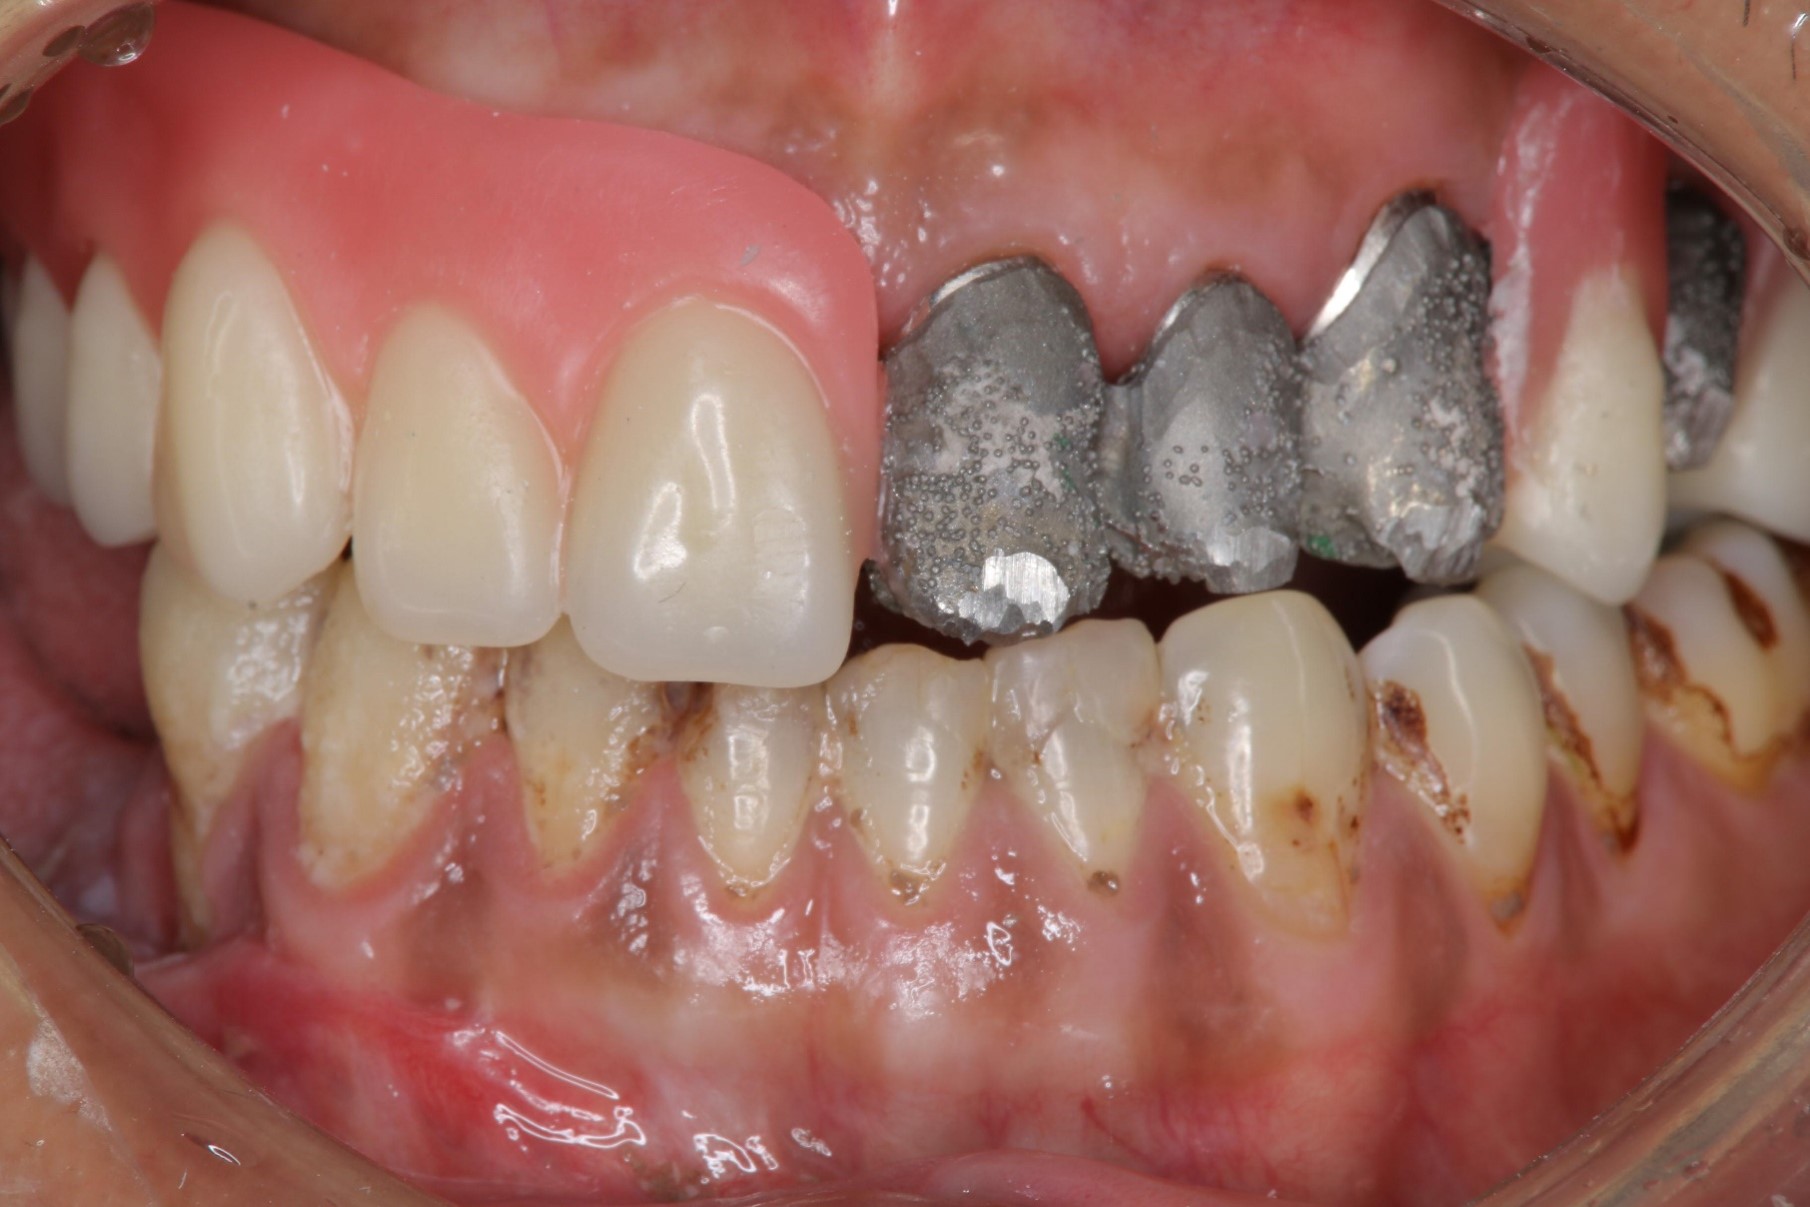

口內試戴

內冠及定位器口內照